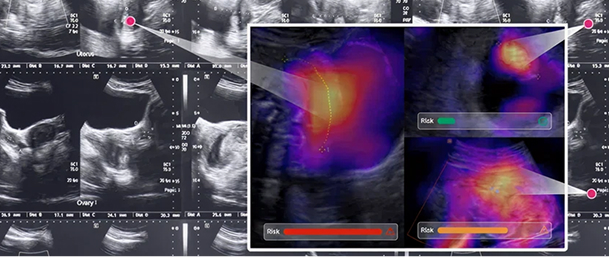

Traditional methods simply count 40 weeks from the last menstrual cycle. Our AI analyzes your baby's growth patterns to predict his/her most likely delivery timing—based on real data, not just averages.

Ultrasound AI uses advanced artificial intelligence to provide personalized delivery date predictions that go beyond traditional calendar-based estimates.